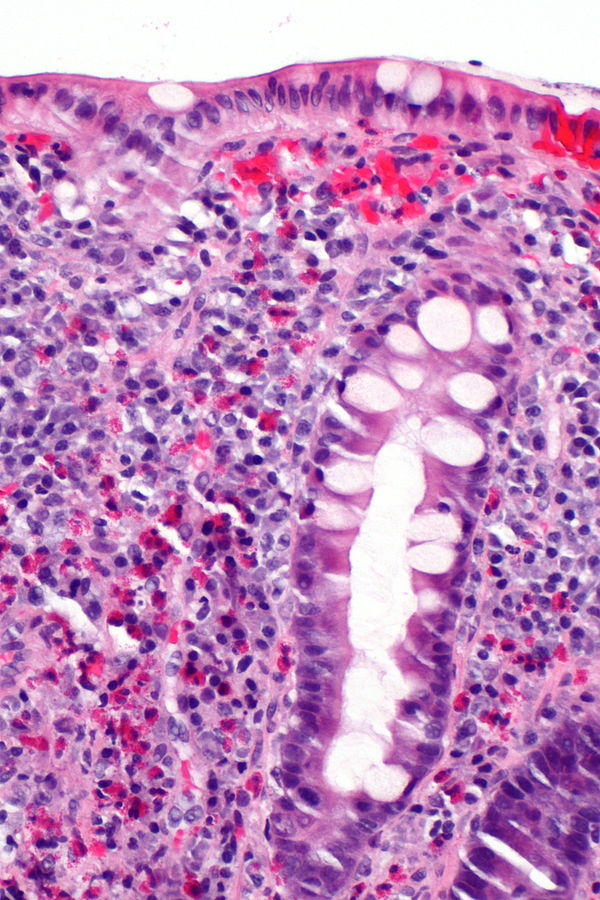

Фотографии объектов и элементов, связанных с цифрой 3

Раздел: Картинки на заметку